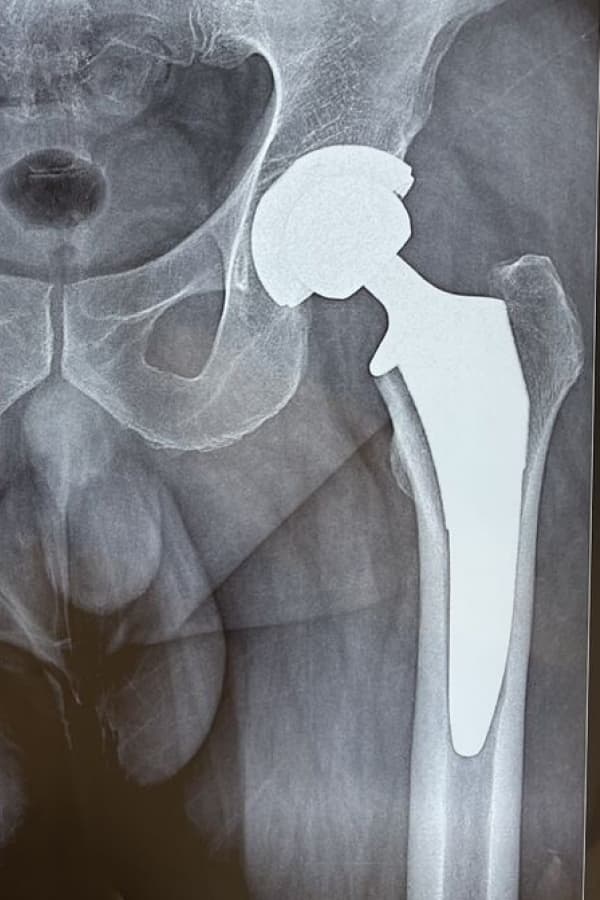

• Direct recreation of leg length and implant positioning with x-ray during surgery

Dr. Applonie offers hip replacement with a muscle sparing approach called the anterior approach. The implant positioning and leg lengths are confirmed directly during surgery. You will begin placing full weight on the hip replacement directly after surgery with the goal to complete physical therapy goals of ambulation and even stairs on the first day of surgery.